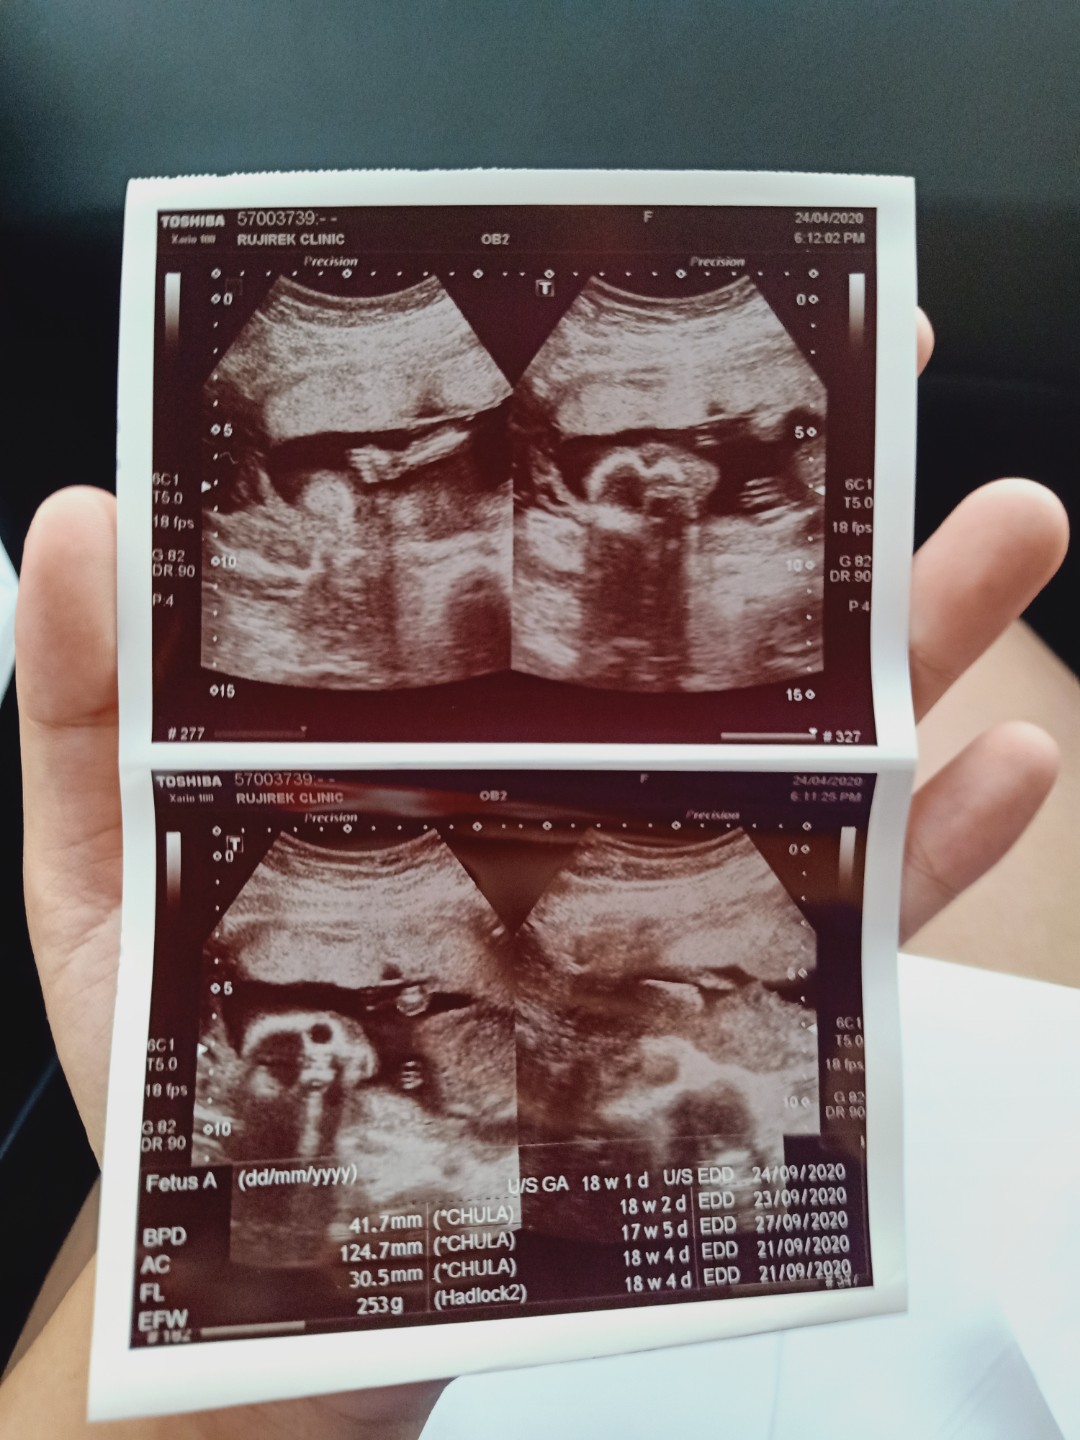

ดีใจมากค้า ได้ลูกชายสมใจ. ขอดูรูปซาวแม่ทีมกันยาหน่อยค้าาาา ได้ลูกชายรึลูกสาวกันน้อ บ้านนี้คนแรกได้ลูกสาวแล้วคนสองหมอบอกลูกชาย ดีใจม้ากกกกกกก